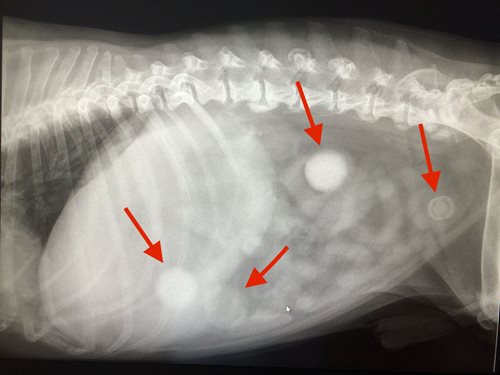

De twee witte bollen zijn springballen

Op de eerste foto (met de witte bollen) ziet u rechts ook een pijltje. Deze pijl wijst naar een grote blaassteen. Soms zijn het vele afzonderlijke blaassteentjes. Deze zijn al wat moeilijker te zien.

Ziet u de kleine witte puntjes in de blaas?